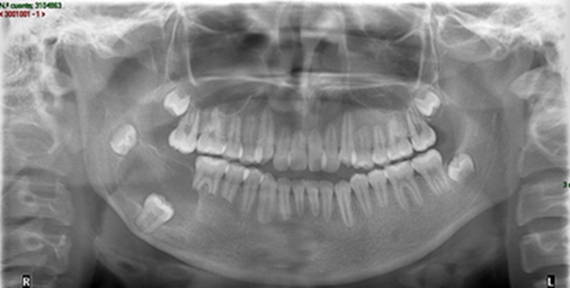

Paciente femenino de 9 años de edad de Valladolid, Yucatán, sin antecedentes patológicos sistémicos; que acude a la Clínica de Endodoncia de la UADY refiriendo traumatismo dental de 4 meses de antigüedad. Clínicamente presentó movilidad y estoma adyacente al diente 2.1, los incisivos anterosuperiores respondieron negativamente a las pruebas térmicas. Radiográficamente se observó formación radicular incompleta y lesiones periapicales en los incisivos centrales superiores.

Plan de tratamiento: revascularización en los órganos dentarios 2.1 y 1.1 y su posterior restauración. Se realizó el protocolo según Trope con dos modificaciones; se reemplazó el hipoclorito de sodio por la solución de agua superoxidada con pH neutro y se disminuyó el tiempo de irrigación de 20 a 5 minutos. A la semana del tratamiento inicial se observó que el estoma remitió, la movilidad cesó y la paciente se encontraba asintomática, se continuó el tratamiento. En los controles realizados durante 22 meses, la paciente se encontró asintomática, se observó el cierre apical del 1.1 y aumento de la porción radicular y disminución de la lesión apical en el 2.1.

CONCLUSIÓN

Este tratamiento con 22 meses de control presenta un éxito clínico y radiográfico, por lo que se recomienda continuar investigando empleando esta técnica ya que utiliza una solución biocompatible que eficienta el tiempo de trabajo.